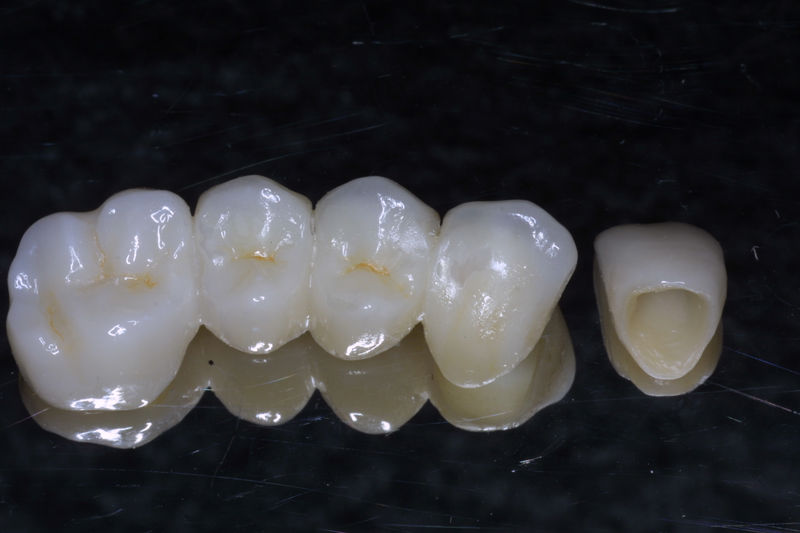

Restauraciones fabricadas en el laboratorio con materiales estéticos, los cuales cubren de manera parcial dientes posteriores. Se utilizan primariamente para restaurar dientes con caries, fracturas y/o defectos amplios. Para poder enviar el caso al laboratorio se toman impresiones utilizando materiales de impresión o técnicas modernas digitales.

Restauraciones fabricadas en el laboratorio con materiales estéticos, los cuales cubren de manera total dientes anteriores y posteriores. Se utilizan primariamente para restaurar dientes con caries, fracturas y/o defectos amplios, así como soportes de puentes. Para poder enviar el caso al laboratorio se toman impresiones utilizando materiales de impresión o técnicas modernas digitales.

Restauraciones fabricadas en el laboratorio con materiales estéticos, los cuales se usan para reemplazar dientes ausentes usando coronas como soporte. Para poder enviar el caso al laboratorio se toman impresiones utilizando materiales de impresión o técnicas modernas digitales.